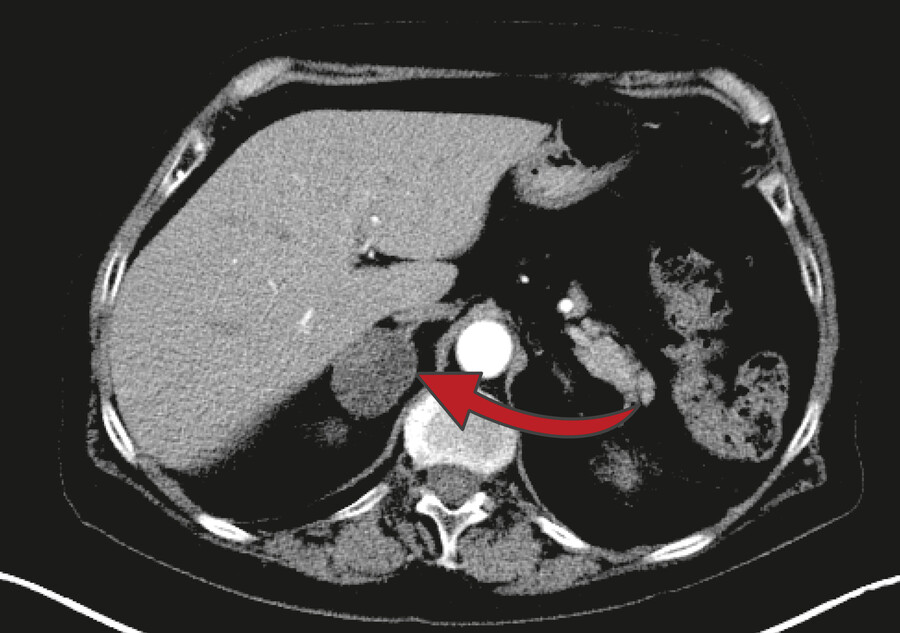

Drei Prozent der über 50-Jährigen haben Nebennierentumore. Bei den über 80-Jährigen ist sogar jeder zehnte betroffen. 80 bis 90 Prozent dieser Tumore, die meist zufällig, zum Beispiel bei einer Computertomographie bei Gallenproblemen, Nierensteinen oder Rückenleiden, entdeckt werden, sind jedoch gutartig und vermeintlich harmlos.